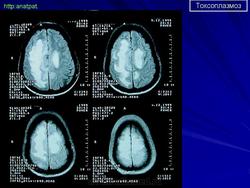

Церебральный токсоплазмоз.

Церебральный токсоплазмоз

Neurotoxoplasmosis